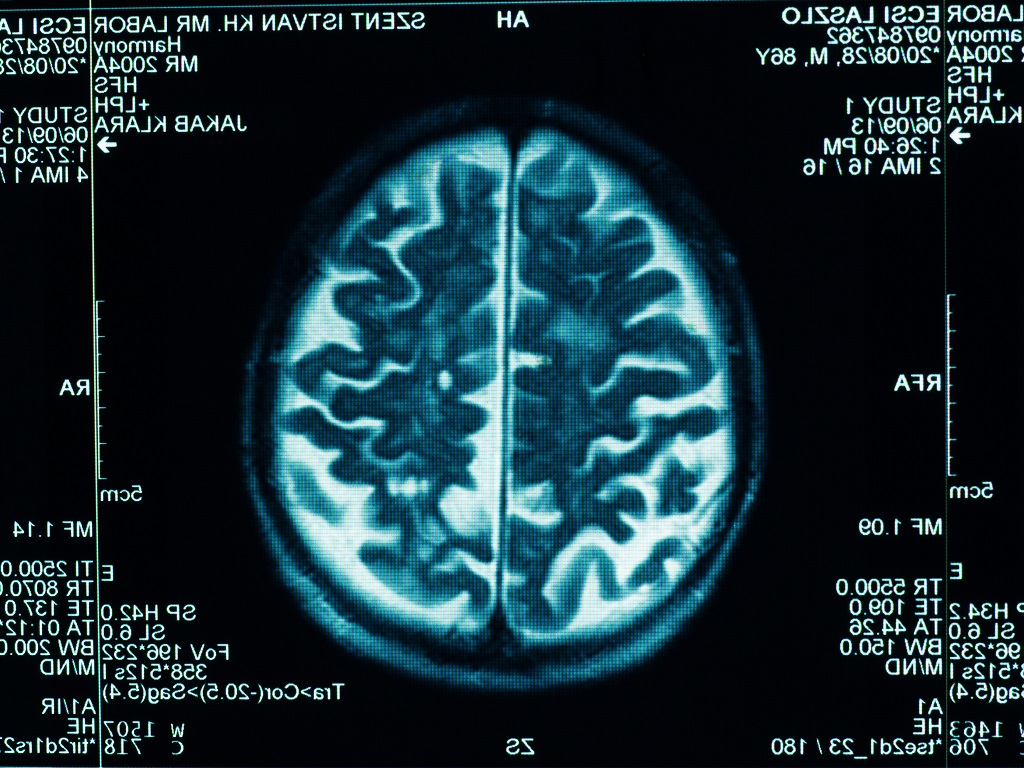

• Neurobiologie: das Körperschema in der Großhirnrinde – Ursachensuche für psychische Erkrankungen (Biologie, Sek I und II, Download Infos)